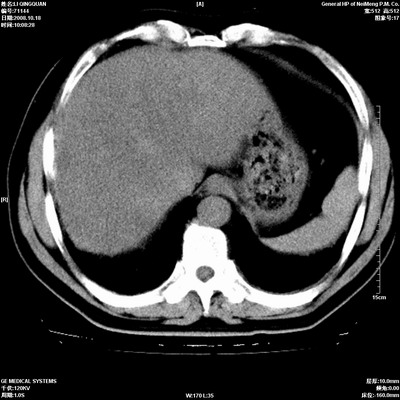

以下是引用ybing在2008-10-19 12:58:00的发言:[br]左肺上叶阻塞性炎症-建议支气管镜进一步检查除外中央型肺癌

以下是引用随光逐影在2008-10-19 14:31:00的发言:[br]考虑左肺中央型肺癌并左肺上叶阻塞性肺炎,肺不张。